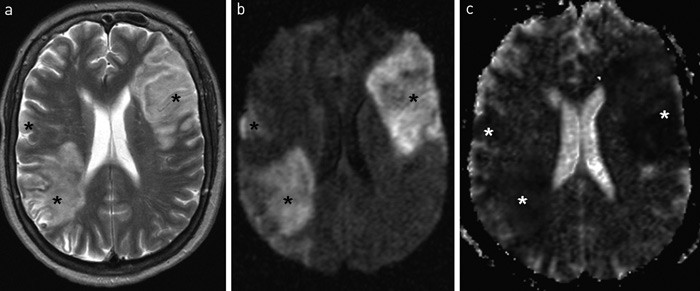

Pasienten ble behandlet med cefotaksim 2 g x 3, metronidazol 500 mg x 3, enoksaparin 40 mg x 2 og forsøksvis faktor VIII-konsentrat og metylprednisolon 1 g x 1. Dag 16 ble hun overflyttet til Rikshospitalet. Hun var da paralytisk i venstre kroppshalvdel, desorientert, men våken. Det ble da foretatt en ny MR-undersøkelse (fig 1). Fra dag 20 til dag 25 falt trombocyttallet fra 200 til 23. Innenfor samme tidsrom utviklet hun makroskopisk hematuri og melena. INR og cephotest lå i normalområdene, fibrinogennivået hadde sunket noe, men lå fortsatt i referanseområdet. D-dimer var 19. Man mistenkte heparinindusert trombocytopeni type 2 (HIT2), og enoksaparin ble seponert dag 22. Acetylsalisylsyre 160 mg x 1 ble valgt som eneste tromboseprofylakse.